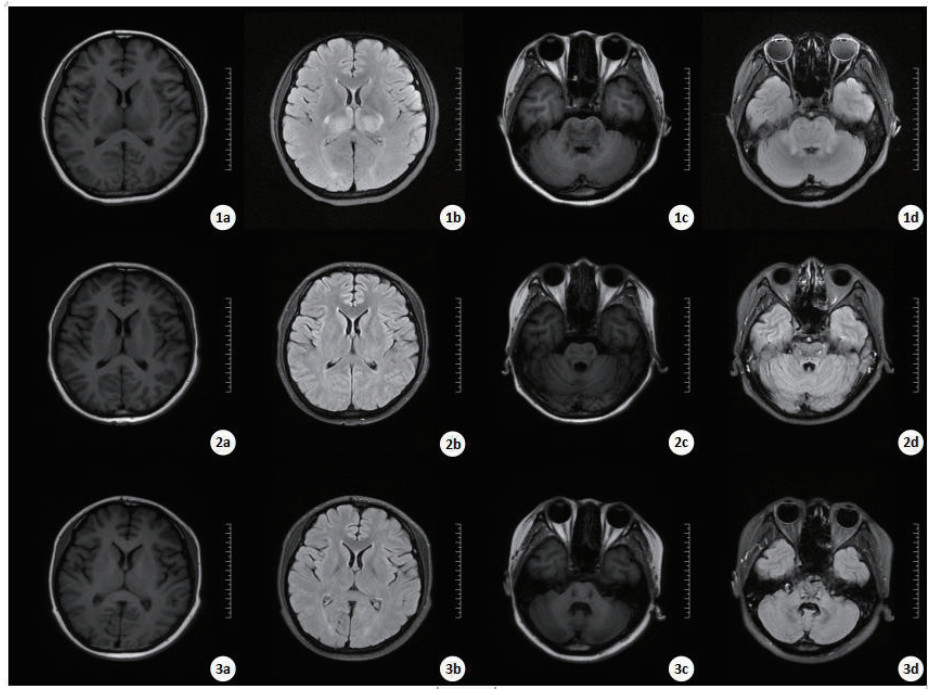

|

| 入院第7天的MRI显示,T1WI(1a和1c)、T2WI(1b和1d): 胼胝体压部、双侧丘脑、双侧基底节区、脑干异常信号。第60天、第105天MRI显示,T1WI(2a和2c、3a和3c)、T2WI(2b和2d、3b和3d): 左侧额叶、右侧顶叶见少许点片状稍长T2信号影,黑水像呈稍高信号。桥脑及中脑可见对称性斑片状长T1长T2信号影,黑水像中心呈高信号,边缘环绕低信号。 图 2 病例2的MRI结果 Fig 2 MRI results of Case 2 |

而病例2未出现癫痫样症状发作,出现昏迷的时间也较晚,影像学检查未见明显脑水肿表现。这种差异性的表现考虑与特定的神经传导通路相关,具体损伤的机制仍在探索中。此外,我们观察到存活的3例患者均为年轻女性,平均年龄19.3岁(26岁、14岁、18岁),DQ导致的神经毒性表现是否与年龄和性别有关,因本研究观察到的病例数较少、暂不能得出有效结论。但有动物实验[24]表明,雌性大鼠比雄性大鼠更容易耐受DQ所致的氧化应激反应。Djukic等[22]用非选择性一氧化氮合酶抑制剂(NG-nitro-L-arginine methylester,L-NAME)预处理可降低DQ的神经毒性作用,并减少应激/亚硝化对DQ诱导的神经毒性的反应。考虑到动物实验中DQ所致脑区损害的差异较大、与人体神经系统损伤有所不同,可能与脑组织血管供应相关,L-NAME在人体内是否存在相同的保护机制仍有待探究。